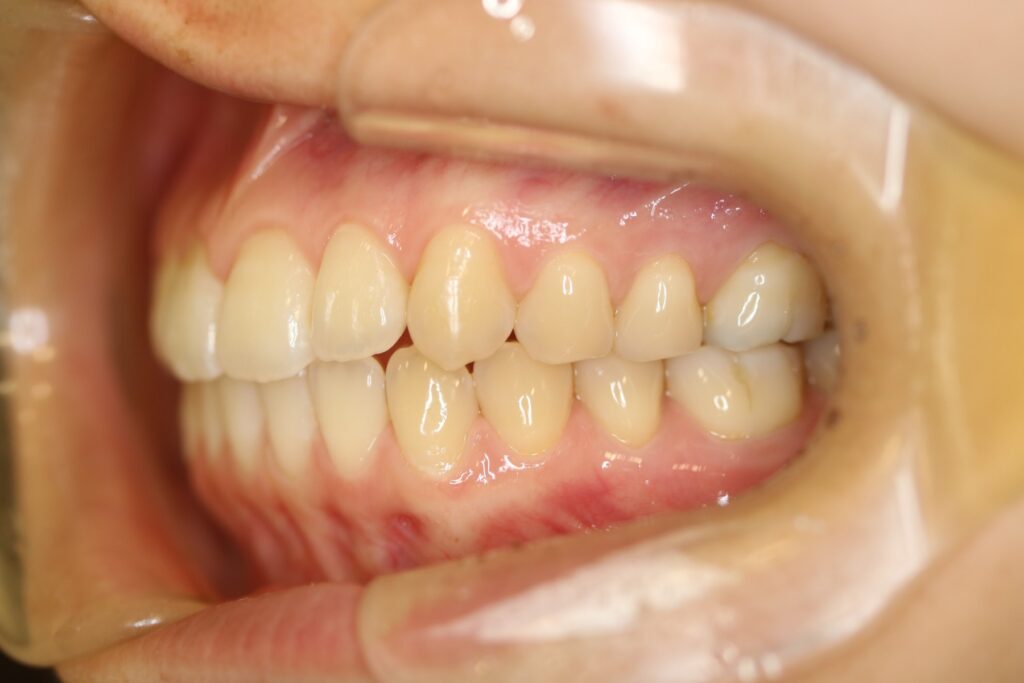

治療実績(症例) アライナー矯正 症例1 上顎前突症例 症例2 上下顎前突症例 症例3 叢生 症例4 開咬 症例5 開咬(外科的矯正治療) アライナー矯正 Post Share Hatena Line RSS feedly Pin it note 1.主訴2.診断名3.初診時年齢4.治療に用いた主な装置とオプション5.抜歯部位6.治療期間・通院回数7.総額と費用内訳総額相談検査・診断料調整料4,000円8.リスク・副作用 治療前 治療中 治療後